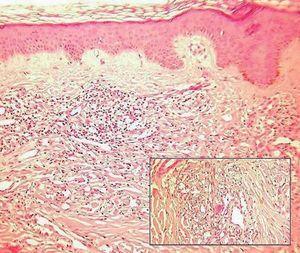

Fig. 3.—Epidermis ortoqueratósica y dermis con neoformación vascular e infiltrado inflamatorio. (Hematoxilina-eosina, ×10.) En el recuadro se observa la presencia de abundantes vasos de diferente tamaño con células atípicas, más abundantes en la parte superior izquierda. (Hematoxilina-eosina, ×40.) Obsérvese la presencia de pigmento hemosiderínico junto a la neoformación vascular.

Encontramos una epidermis ortoqueratósica y en la dermis se observaba una neoformación vascular con vasos de distinto tamaño y células atípicas en su interior. Llamaba la atención la presencia de un infiltrado inflamatorio abundante. Próximo a los vasos neoformados se apreciaba la presencia de pigmento hemosiderínico. Con la tinción de ácido peryódico de Schiff (PAS) se tiñeron algunos cuerpos de inclusión (figs. 3 y 4).